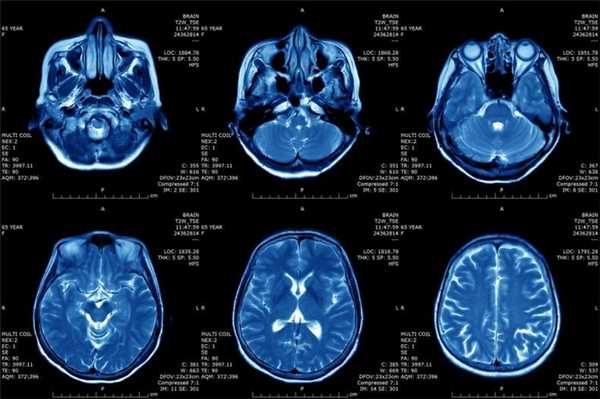

Магнитно-резонансная томография играет важную роль в обнаружении опухолевых процессов различной локализации. Высокая детализация внутренних структур позволяет выявить рак на ранней стадии, что важно для прогноза. Лечением опухолевой патологии занимается онколог.

Можно ли на МРТ увидеть рак? Магнитно-резонансное сканирование особенно эффективно при обнаружении некоторых типов опухолей головного и спинного мозга, первичных новообразований костей, сарком мягких тканей. При раке шейки матки, мочевого пузыря МР-исследование лучше, чем КТ показывает, насколько глубоко новообразование проникло в соседние структуры, является ли ткань опухолевой или рубцовой.

Пациенту с подозрением на онкологический процесс МРТ назначают в качестве первичной диагностики, для определения стадии рака, измерения кровотока. Результаты сканирования помогают онкологам планировать лечение — например, хирургическое вмешательство или лучевую терапию, своевременно выявить рецидив: продолженный рост опухоли, метастазирование.

"МРТ — высокочувствительный метод, основанный на анатомической и функциональной информации, поэтому он часто выявляет злокачественные изменения, которые не проявляются в клинических тестах или плохо определяются другими методами визуализации. Таким образом, МРТ является лучшим инструментом для обнаружения и оценки опухоли на начальной стадии заболевания."

При МРТ головного мозга в левом мосто-мозжечковом углу определялось больших размеров округлой формы внемозговое патологическое образование, с четкими ровными контурами, широким основанием, прилежащее к твердой мозговой оболочке. После внутривенного контрастирования отмечалось равномерное, выраженное усиление интенсивности МР-сигнала от вышеописанного образования, а также твердой мозговой оболочки. Пациенту был поставлен диагноз (менингиома левого мосто-мозжечкового угла).